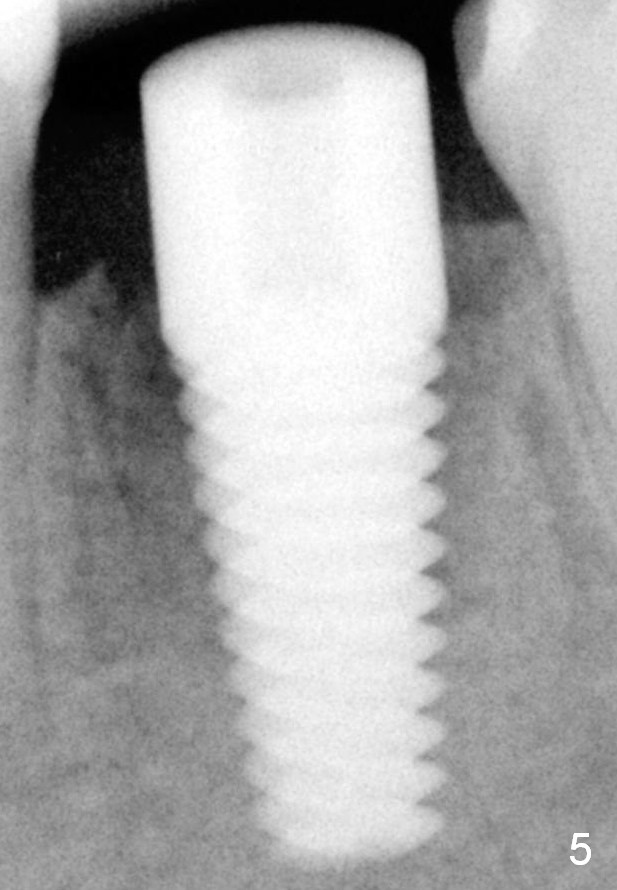

Fig.5 (immediately postop): A 6x17 mm implant is placed.